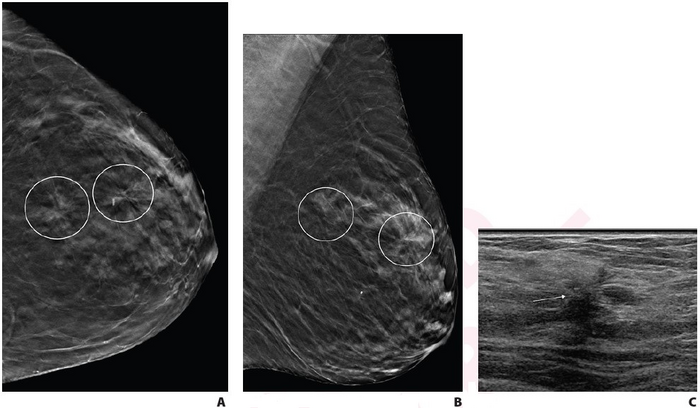

image: A. Craniocaudal and B. mediolateral oblique digital breast tomosynthesis images demonstrate two areas of AD in upper outer left breast (circles) that persisted on additional diagnostic tomosynthesis images (not shown). C. Transverse greyscale ultrasound image of upper outer breast shows irregular hypoechoic mass with associated AD at 12:30 (arrow), corresponding to posterior AD. No ultrasound correlate was identified for anterior AD. Ultrasound-guided biopsy of posterior AD revealed malignancy (invasive lobular carcinoma). Tomosynthesis-guided biopsy of anterior AD yielded benign pathology (stromal fibrosis). view more

Leesburg, VA, July 27, 2022—According to ARRS’ American Journal of Roentgenology (AJR), for patients with multiple architectural distortion (AD) identified on digital breast tomosynthesis (DBT), biopsy of all areas may be warranted, given the variation of pathologic diagnoses across AD in individual patients.

“Multiple AD, compared with single AD, was significantly more likely to yield high-risk pathology, but there was no significant difference in yield of malignancy,” wrote corresponding author Lilian C. Wang, MD, of Northwestern Medicine. “In patients with multiple AD, multiple ipsilateral or contralateral AD commonly varied in pathologic classification: benign, high risk, or malignant.”

Ultimately, compared with single AD, multiple AD showed a higher frequency of high-risk pathology (53.0% vs. 32.5%, p=.002) but no significantly different frequency of malignancy on a per-lesion or per-patient basis (31.8% vs. 28.2%, p=.56). In 8/24 patients with ≥2 ipsilateral biopsied AD, the ipsilateral areas varied in terms of most aggressive pathology; in 5/10 patients with contralateral biopsied AD, the contralateral areas varied in most aggressive pathology.